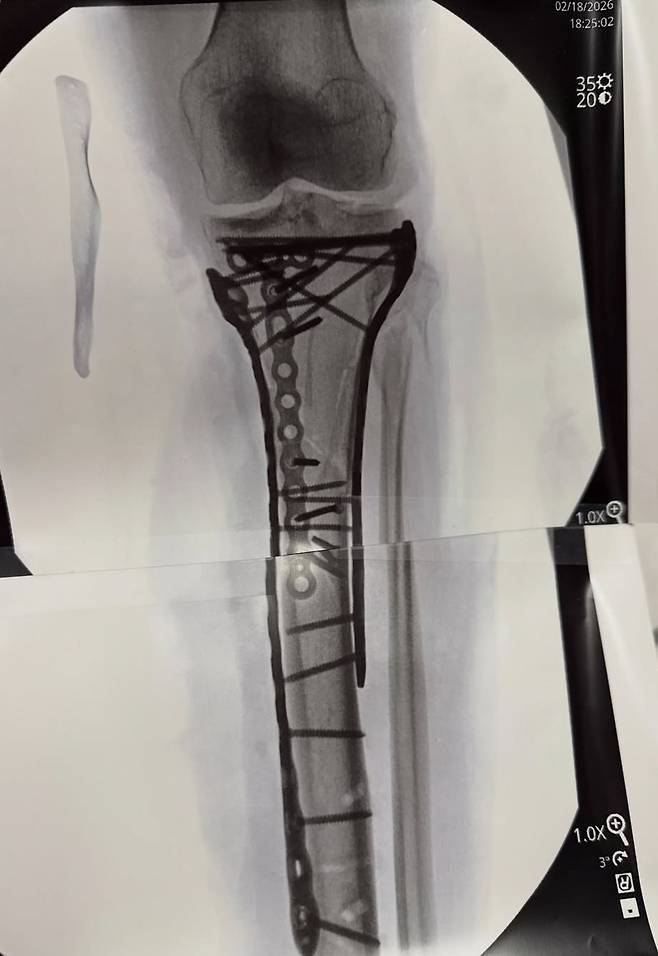

본은 무려 5차례나 대수술을 받았다. 그는 최근 치료 과정을 담은 영상과 글을 올렸다. 본은 "항상 모든 일에는 이유가 있다고 말하지만, 만약 내가 전방십자인대 파열 부상을 당하지 않았더라며, 톰 해켓 박사님이 내 곁에 없었을 거고, 내 다리를 구할 수도 없었을 거다. 해켓 박사님이 내 목숨을 구해 주셨다. 다리를 절단하지 않도록 해주셨다"며 "오른쪽 발목도 부러져서 당분간 휠체어를 타야 할 것 같다. 조만간 목발을 짚고 걸을 수 있기를 바라지만, 두고 봐야한다. 하지만 재활에 전념해서 최대한 빨리 회복할 수 있도록 노력할 거다. 늘 그랬듯이 한 단계씩 차근차근 나아갈 거다"라고 밝혔다.

그는 금속판과 나사가 박힌 엑스레이 사진도 공개했다. 본은 올림픽에서 총 3개의 메달을 따냈다. 2010년 밴쿠버 대회에서 활강 금메달, 슈퍼대회전에서 동메달, 2018년 평창 대회에선 활강 동메달을 목에 걸었다. 2014년 소치 대회는 부상으로 불참했다.